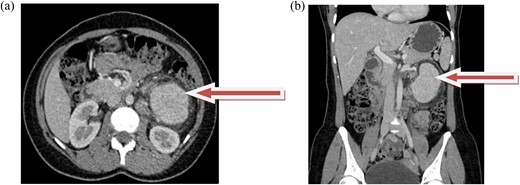

Laparoscopic transperitoneal tumorectomy was performed. During the transperitoneal approach, the tumor was observed anterior to the left kidney (Fig. 2a and b).

(a and b) The images show the laparoscopic view of a left retroperitoneal mass.